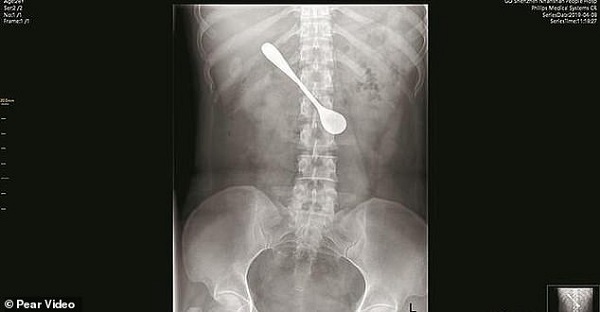

Phim chụp X-quang cho thấy vị trí chiếc thìa mắc kẹt trong tá tràng bệnh nhân - Ảnh chụp màn hình. |

Bà đến Bệnh viện Nam Sơn Thâm Quyển ở thành phố Thâm Quyến, tỉnh Quảng Đông (Trung Quốc) để khám. Hình ảnh chụp X-quang cho thấy cái muỗng nằm trong tá tràng, tức đoạn đầu ruột non, phần tiếp sau của dạ dày.